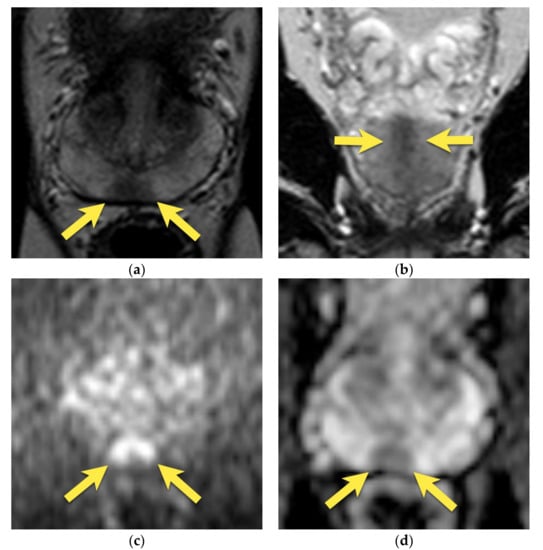

5. Hypointense Area in the Median Posterior Middle Gland or at the Base